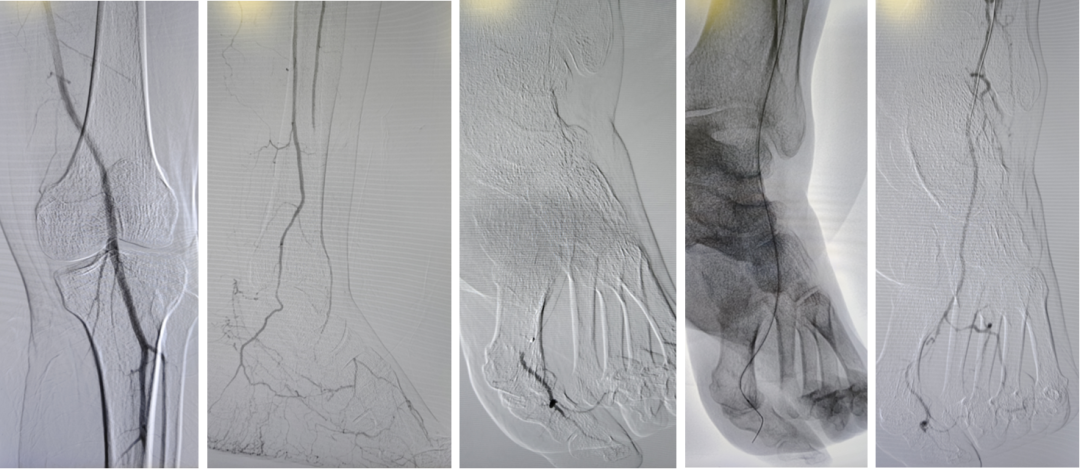

Case 4:另一例膝下三支闭塞,仅腓动脉远端通过侧支供应足底。正向开通腓动脉后,胫后及胫前仍无法进入真腔,遂穿刺足底动脉,将导丝逆行送至踝部,与正向导丝会师后完成扩张,最终开通足底动脉。

★ 导丝对吻技术与CART技术

当逆向导丝无法进入正向真腔时,可采用导丝对吻技术:将逆向导丝留置作为标记,引导正向导丝前进。若两者均在假腔内,则可应用球囊扩张假腔(CART或Reverse-CART),为导丝进入真腔创造条件。

Case 5:正向导丝经胫前进入,逆向导丝经足底上行,在踝部无法汇合。先后扩张正向球囊和逆向球囊后,导丝顺利进入同一腔道,成功开通足弓。

Case 6:采用双球囊对吻技术:正向使用外周球囊,逆向使用冠脉球囊,在6F鞘内同时扩张2mm重叠段,导丝顺利通过。